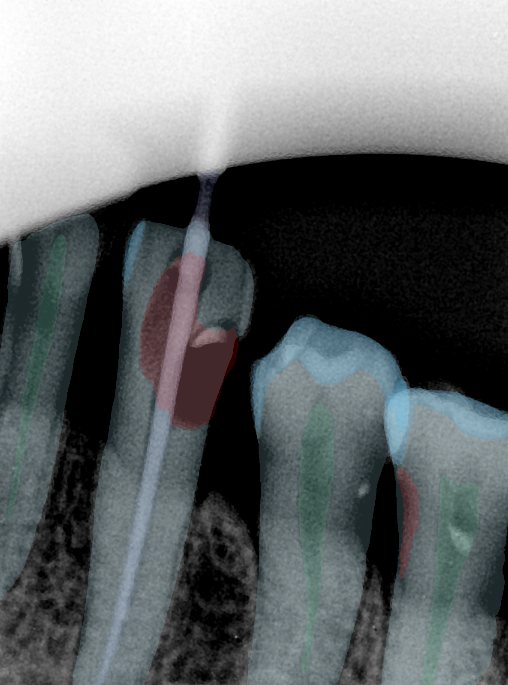

CR/DR 牙齿分割阶段记录

当前进展

- 完成了 CR/DR 牙齿相关分割训练

- 当前结果已经达到阶段预期,但仍有细节问题需要继续处理

相关测试

遇到的问题

- 训练过程中出现过 mask 下移问题

- 部分结果会出现 box 填充异常

- mask 边缘仍然有比较明显的锯齿感

参考

第二版算法问题测试